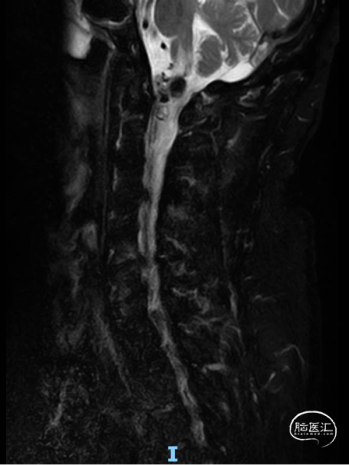

术前颈椎MR

CCJ AVF 栓塞后复发,术区及以下脊髓水肿,变性

术后一周MR,提示脊髓水肿较前减轻